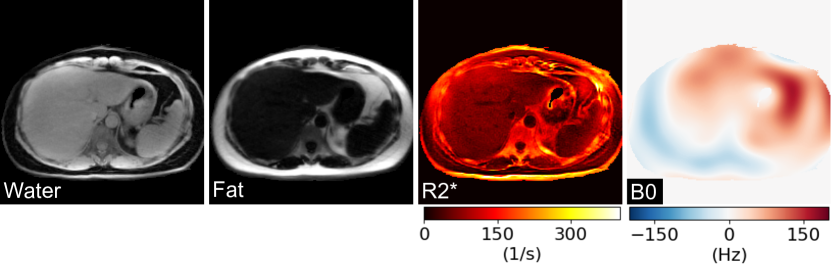

Refer to caption

Figure 7: (A) Reconstructed 4 complex coefficient maps (only magnitude is shown) using the linear subspace method for a human brain study. (B) Synthesized images (at inversion time 40 ms, 400 ms, 800 ms, 4000 ms) using (top) the above 4 complex coefficient maps of the linear subspace method and (bottom) the 3 physical maps of the nonlinear model-based reconstruction, respectively. The corresponding T1 maps are presented in the rightmost column.

With the above settings, Fig. 7 (A) depicts the four main coefficient maps estimated using the linear subspace method for a brain study. In this case, a joint 1subscript1\ell_{1}-Wavelet sparsity regularization was applied to the maps with a strength of 0.00150.00150.0015 to improve the precision. For this dataset, the reconstruction together with a pixel-wise fitting took around 2 minutes on the GPU. Fig. 7 (B) presents the synthesized images along with the corresponding T1 maps using (top) the above four coefficient maps for the linear subspace and (bottom) the 3 physical parameter maps for nonlinear model-based reconstructions, where a similar joint 1subscript1\ell_{1}-Wavelet sparsity is applied with the regularization parameter 0.090.090.09. Again, both linear subspace and nonlinear methods could generate high-quality synthesized images and T1 maps while the nonlinear methods have slightly less noise and better sharpness.